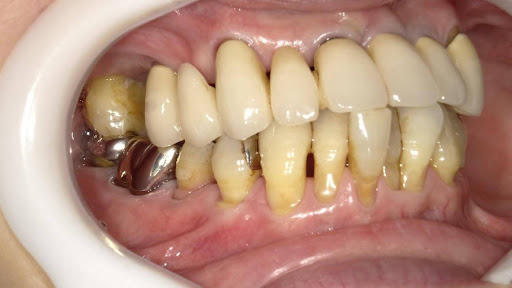

After

枚方市のインプラントの症例

M・I 様 女性 70代

症状としては、左下56は、歯周病で欠損したと考えられるが、かなりの骨欠損をともなっていた。左上456に関しては、動揺が大きく、炎症が起き、排膿、および、歯性上顎洞炎を起こしていた。

治療法としては、動揺がひどくなってきて、炎症の症状もあったため、左上56の抜歯を希望。インプラント治療をその後、希望したため、左上4に関しては抜歯即時埋入。左上6に関しては、既存骨1から2mmでインプラント治療が厳しい状態であったが、グラフトレスサイナスリフトを行い、治療期間5か月はかかるということを説明して、インプラント埋入をおこないました。その後、2か月半後、大幅に骨が欠損している下顎56に対して、ショートインプラントを使用して、下顎神経の損傷を避けて、インプラント埋入を終えています。その後2か月後に光学印象で印象を行い、上顎刺億456歯、3ユニットのジルコニアブリッジを装着。下顎左側56に関しては、骨欠損が大きいため、歯冠長がだいぶ長くなるため、ジルコニアの連結冠を装着して治療を終えた。

治療結果は、上顎6に関しては、既存骨が少なく、厳しい治療ではありましたが、5か月で治療を終え、患者様の負担を最小限に抑えるができたと考えます。(従来のサイナスリフトでは、このようなケースでは1年以上、1年程度の治療期間がかかるか、治療が不可能と言われるケースだと考えます。)また、下顎は骨欠損が大きく、下歯槽管のリスクが起きることが考えられますが、ショートインプラントを使用することで安全に治療を行うことができました。

治療の期間・回数:治療期間5か月(上顎456 3ピースブリッジの治療は5か月(上顎既存骨が2mm程度しかなく、骨結合に時間がかかるケースであったために、5か月の治療期間が必要であった。)(左下56に関しては2か月半で治療を終えています。)治療回数は、13回。

治療の価格:1,474,000円(税込)

治療費の内訳:左上46および左下56のインプラント基本料(フィックスチャー及び手術費用、投薬費用、レントゲン費用、インプラント上部費用(アバットメントおよびジルコニアクラウンの費用用)330000円(税込み)×4本分 1320000円(税込)。左上5ジルコニアポンテック費用88000円(税込)。オプション費用、左上4抜歯即時埋入加算(人工骨費用を含む)+グラフトレスサイナスリフト費用 33000円(税込)、左上6グラフトレスサイナスリフト費用 33000円(税込)

治療のリスクや副作用:手術後に、痛みや腫れ、出血、合併症などを引き起こす可能性があります。噛む感覚がご自身の歯と異なる場合があります。見た目がご自身の歯と異なる場合があります。手術後にメインテナンスを継続しないと、インプラントが抜け落ちる可能性があります。